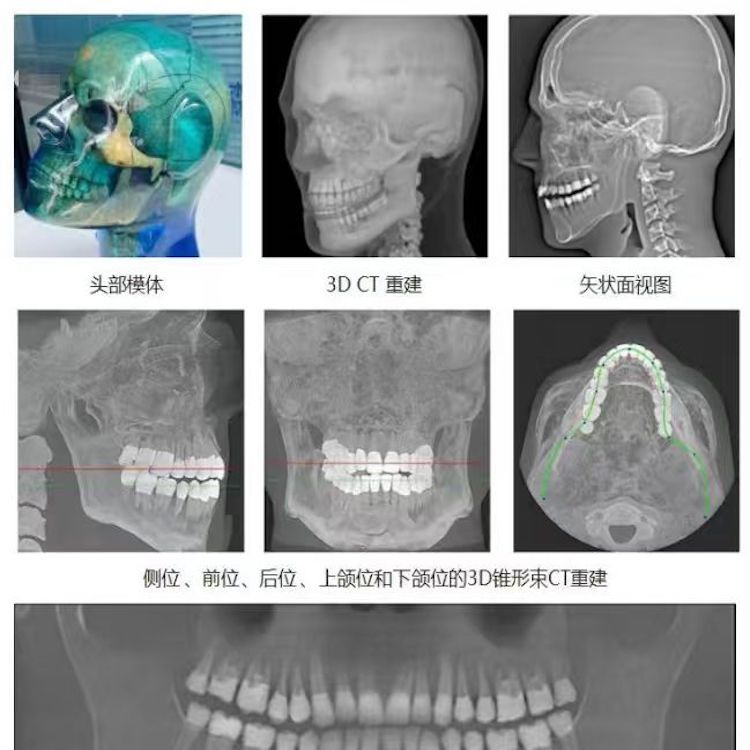

頭部模體

頭部模體是頭部診斷放射學(xué)的參考標(biāo)準(zhǔn),該模體旨在協(xié)助技術(shù)和臨床人員,在大多數(shù)需要精細(xì)解剖細(xì)節(jié)的放射學(xué)程序中選擇、監(jiān)測(cè)、培訓(xùn)和驗(yàn)證掃描參數(shù)。 模體為研究人員、臨床醫(yī)生和技術(shù)人員提供了一致性的工具。它非常適合確定最佳系統(tǒng)設(shè)置、調(diào)試新設(shè)備、監(jiān)測(cè)系統(tǒng)性能和培訓(xùn)牙科X射線、全景X射線、CT和錐束CT程序。 這個(gè)模體包括一個(gè)可調(diào)節(jié)的支架,用于在錐束 CT 或全景X射線系統(tǒng)中定位。模體的下頜略微張開,前牙垂直排列,以復(fù)制正確的咬合引導(dǎo)定位 。 請(qǐng)注意,實(shí)際咬合引導(dǎo)無法在這個(gè)產(chǎn)品中定位。 頭部模體是由專有組織等效材料制成的。由組織模擬樹脂制成,這些樹脂模擬X射線對(duì)人體的衰減特性,適用于CT和治療能量范圍(50keV-25MeV)。 模體在大小和結(jié)構(gòu)上都近似于平均男性頭部 。該模體包括詳細(xì)的3D擬人化解剖結(jié)構(gòu), 包括大腦、骨骼、喉、氣管、鼻竇、鼻腔和牙齒。骨骼包括皮質(zhì)和骨小梁的分離。牙齒包括明顯的牙本質(zhì)、牙釉質(zhì)和包括神經(jīng)的牙根結(jié)構(gòu)。鼻竇完全張開。

頭部模體特點(diǎn) 1. 詳細(xì)的解剖特征; 2. 確定法蘭克福平面以確保正確對(duì)齊; 3. 50 keV 至 25 Mev 的組織等效值; 4. 具有六個(gè)自由度的定位支架; 5. 包括泡沫內(nèi)襯手提箱; 6. 12個(gè)月保修。

功能和應(yīng)用 1. X射線 ,全景X射線 ,CT和錐束CT系統(tǒng); 2. 學(xué)習(xí)如何正確定位頭部以獲得最佳圖像; 3. 測(cè)試重建技術(shù)和算法 ,用于植入物規(guī)劃和頜面部重建; 4. 在實(shí)施新設(shè)備和新技術(shù)期間培訓(xùn)并評(píng)估人員; 5. 驗(yàn)證圖像質(zhì)量的一致性。